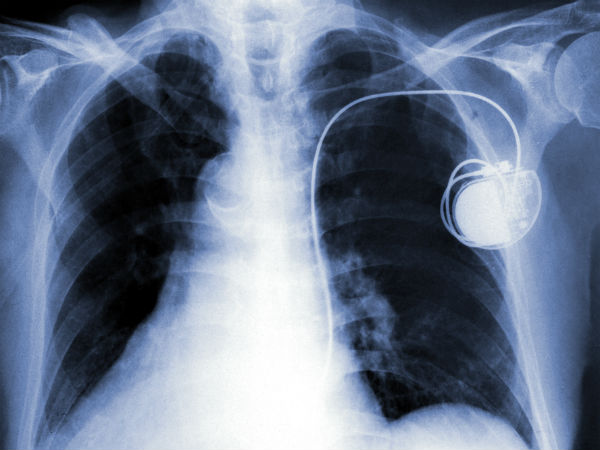

ஃபேஸ்மேக்கர்

இதய பாதிப்பு உண்டாகி ஃபேஸ்மேக்கர் வைத்திருக்கும் பெண்கள் தவறுதலாக கூட ஸ்மார்ட் போனை பிராவில் வைக்கக் கூடாது. சிக்னல் தாக்கத்தால் ஃபேஸ்மேக்கர் செயல் தடைப்பட்டு போய்விடும்.